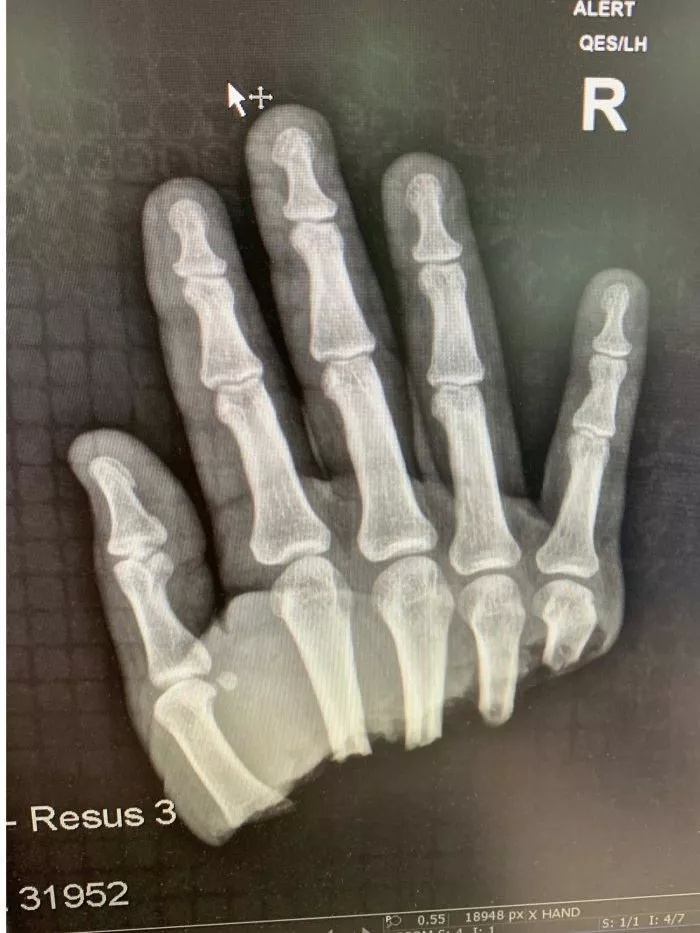

从X光中可以看到,斩断处位于五根手指的下方,说整个右手被切没了也不夸张。

(图片来源:ABC News)